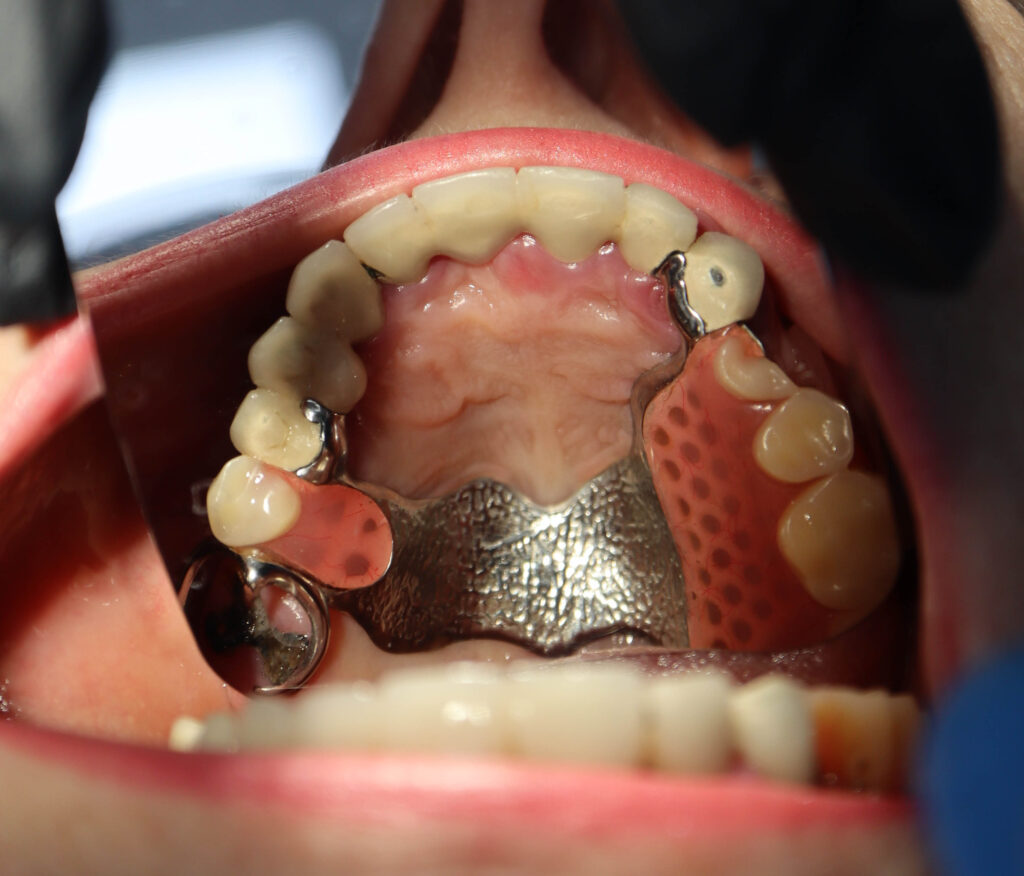

процесс имплантации

Процесс работы

Что было сделано:

Было произведено удаление зубов на верхней челюсти и проведена комплексная имплантация по системе All-on-6.

Установлены 6 имплантатов Megagen AnyRidge.

Спустя 7 дней на верхней челюсти зафиксирован временный металлоакриловый протез из 12 зубов.